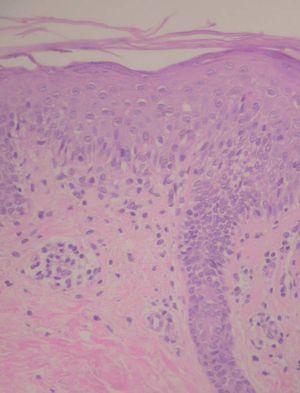

Se trata de un varón sano de 3 años, sin antecedentes personales ni familiares de interés, que fue atendido en nuestra consulta por la aparición de lesiones cutáneas en el abdomen desde hacía 3 meses. La erupción cutánea era asintomática, cursaba en brotes y dejaba una hipopigmentación lenticular residual en las zonas de regresión. El cuadro no se modificaba tras el tratamiento con corticoides tópicos de potencia moderada y alta, pero mejoraba levemente durante el verano en las zonas fotoexpuestas. En la exploración física se apreciaban pápulas descamativas eritematoparduzcas de 3 a 5 mm de diámetro en la zona abdominal inferior y ambas ingles. La descamación de las lesiones consistía en una única escama de aspecto micáceo, la cual era fácilmente desprendible con el rascado (figs. 1 y 2). El resto de la exploración clínica fue normal. En el estudio histológico se observaba una epidermis con acantosis irregular y extensas áreas de paraqueratosis confluente. En la dermis superficial existía un leve infiltrado linfocitario perivascular con afectación focal de la interfase, exocitosis y aislados queratinocitos necróticos (fig. 3). En la actualidad, el paciente tiene 9 años de edad y sigue presentando brotes recurrentes y autolimitados de lesiones cutáneas similares a las descritas que se localizan siempre en la zona abdominal inferior. Una segunda biopsia realizada en el transcurso del proceso demostró hallazgos histológicos similares a los descritos más arriba.

Figura 3. En el estudio histológico se aprecia una dermatitis de interfase con queratinocitos necróticos en la capa basal, exocitosis linfocitaria y un infiltrado inflamatorio leve en la dermis superficial.(Hematosilinaeosina, ×40.)